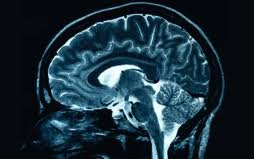

Laboratóriumban növesztett agysejteken vizsgálták a Down-szindróma kialakulásának okát. A betegséget okozó hibás gén az értelmi fogyatékosság mellett számtalan fizikai jelet is produkál. A vizsgálat megállapította, hogy a betegek agysejtjei közötti kommunikáció jóval lassabb, mint egészséges társaiknál - írja a BBC.

Jelen tanulmányt Anita Bhattacharyya, a Wisconsin-Madison Egyetem neurológusa vezetésével készítették. A kísérleti vizsgálat során két Down-szindrómás páciens bőrsejtjéből laboratóriumban őssejt segítségével növesztettek agysejtet. Ez az egyik módja ugyanis annak, hogy megnézzék mi történik a betegek agysejtjeivel fejlődés közben, ami a Down-szindrómát okozza.

Az egyik jelentős eredmény az volt, hogy csökkent a kapcsolat az idegsejtek között. 'Kevesebben és lassabban közlekednek' - mondta Anita Bhattacharyya. Az agysejtek szinapszisokon keresztül kommunikálnak egymással. A szinapszisok számát és aktivitását tekintve a Down-szindrómásoknál ez 60 százalékkal kisebb, mint az egészséges embereknél.